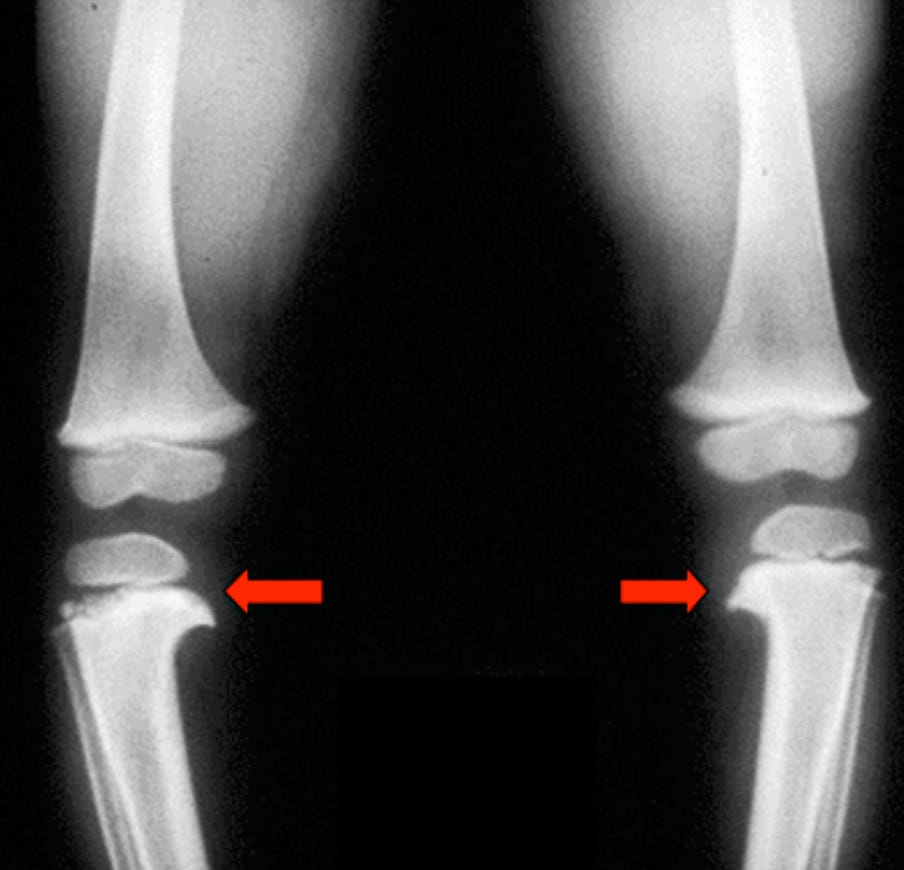

Рентгенологические признаки:

Варусная деформация проксимального отдела большеберцовой кости

Медиальное "клювовидное" выпячивание проксимального метафиза большеберцовой кости

Нисходящий наклон проксимального метафиза большеберцовой кости

МД угол большеберцовой кости >16° (хотя этот признак не является диагностическим)

Соотношение МД углов бедро:голень <1

Угол между метадиафизарный угол измеряется на переднезаднем рентгеновском снимке коленного сустава в положении стоя следующим образом: 1) проводится линия вдоль продольной оси большеберцовой кости (линия 1); 2) проводится линия через вершины проксимального метафиза большеберцовой кости (линия 2); 3) проводится линия, перпендикулярная линии 1, в точке пересечения линий 1 и 2 (линия 3); 4) измеряется угол между линиями 2 и 3 — это и есть угол между метафизом и диафизом большеберцовой кости. Значение угла ≤11° указывает на физиологическую, а не патологическую О-образную деформацию. У этого пациента с болезнью Блаунта метадиафизарный угол равен примерно 18°.